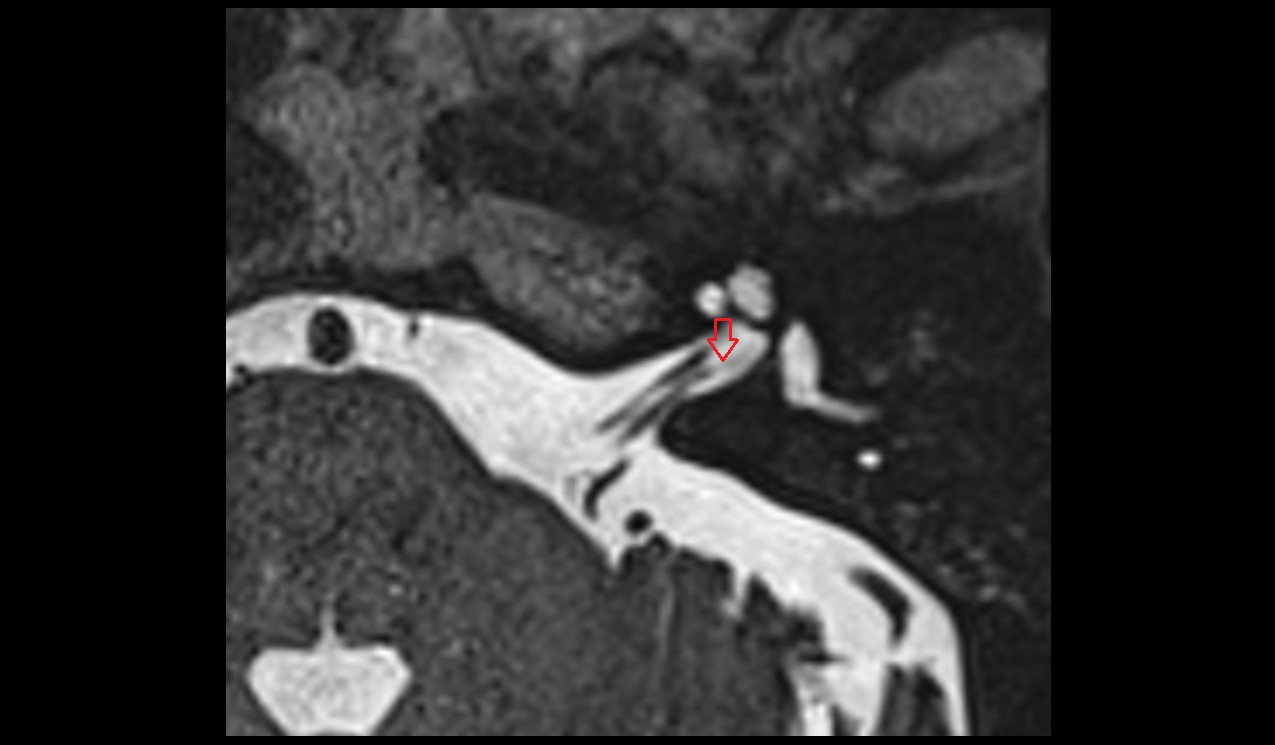

- Articular eminence

- Articular surface of mandibular fossa

- Articular tubercle

- Attachment of inferior head of lateral pterygoid muscle

- Attachment of superior head of lateral pterygoid muscle

- Intermediate zone of articular disc

- Superior retrodiscal layer

- Superior synovial membrane of temporomandibular joint

- Temporomandibular joint

- Mandibular condyle

- Mandibular fossa

- Superior head of lateral pterygoid muscle

- Inferior head of lateral pterygoid muscle